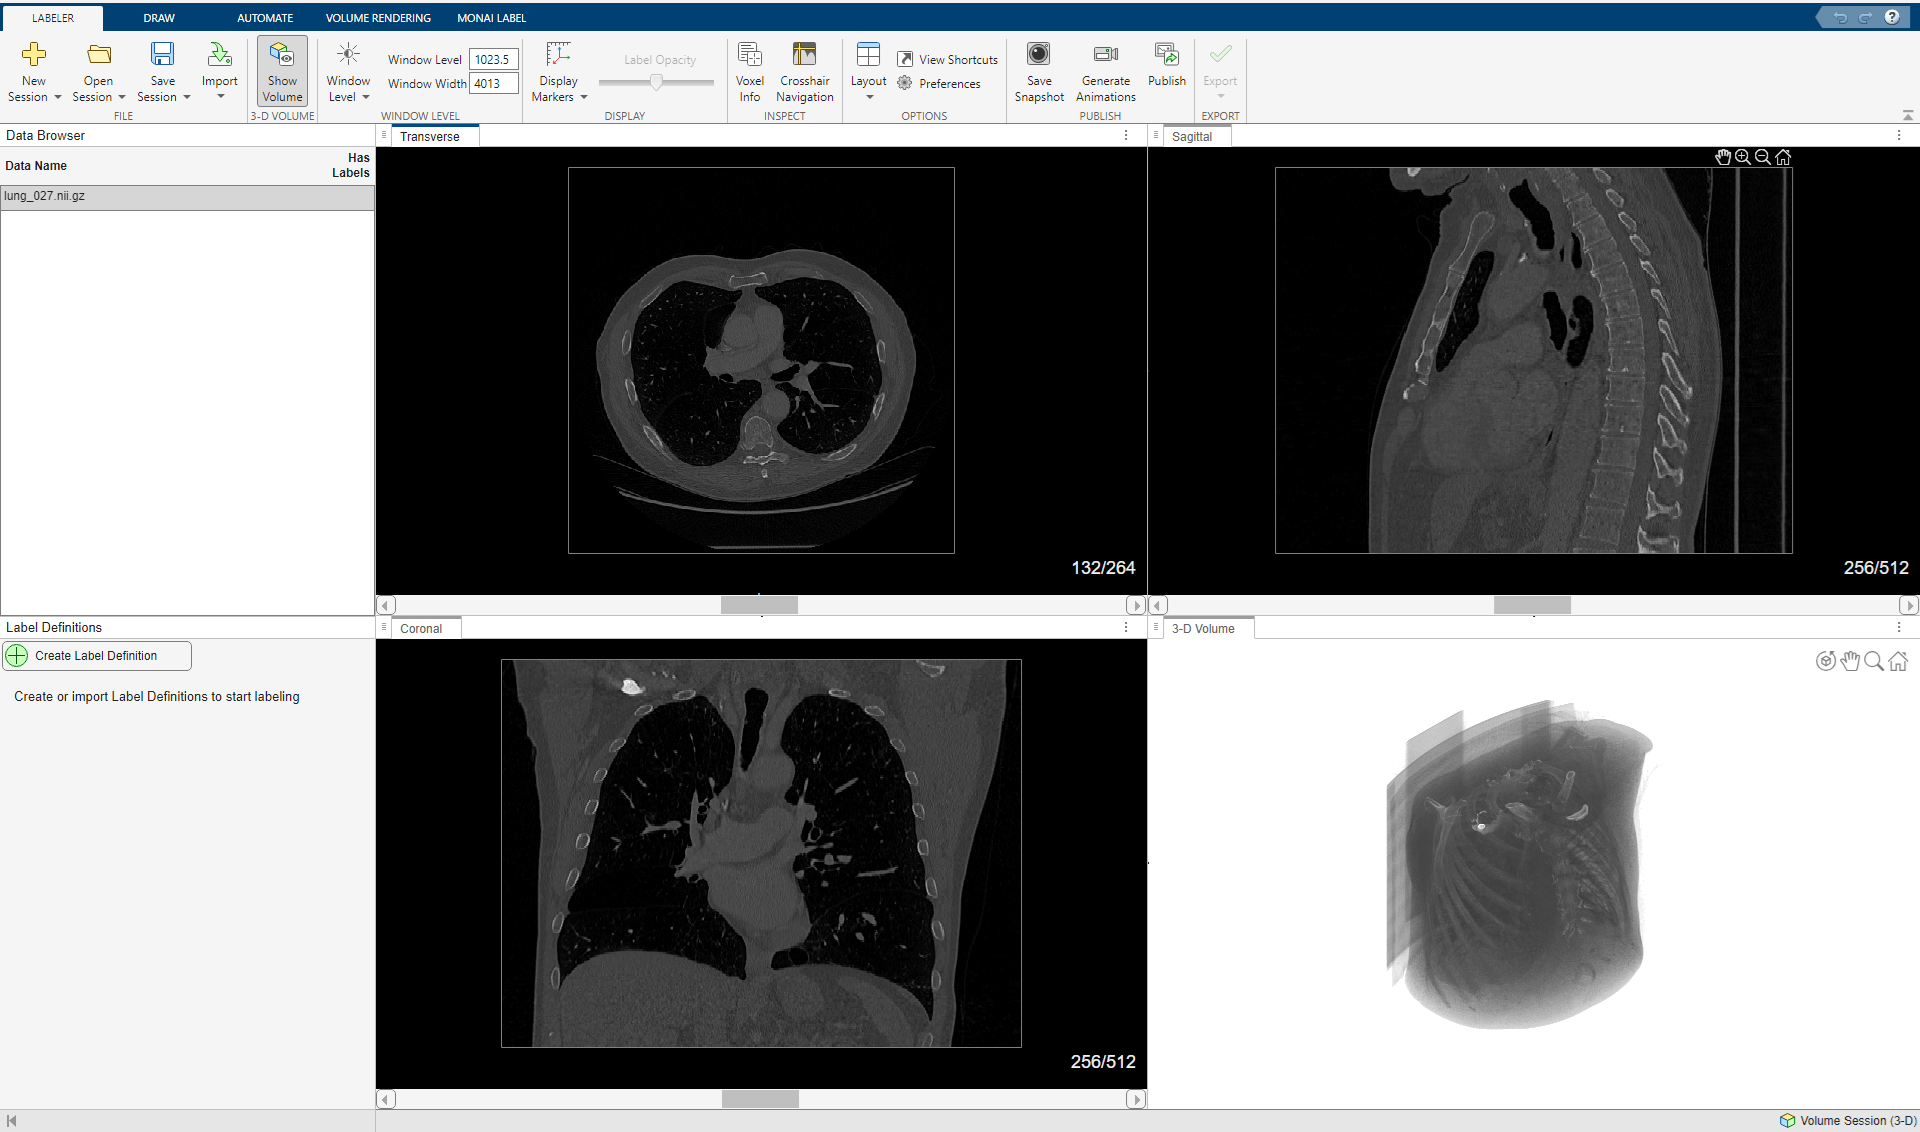

Open Labeling Session and Load Data

Open the Medical Image Labeler app and start a volume labeling session. You can create a new volume session or reopen a previous session. If you create a new session, import the file lung_027.nii.gz from the downloaded data, located in the folder specified by the dataFolder variable. For an example that shows how to create a volume session and import data, see Label 3-D Medical Image Using Medical Image Labeler.

Visualize the labels in different cross-sections of the volume in the 3-D volume rendering pane.